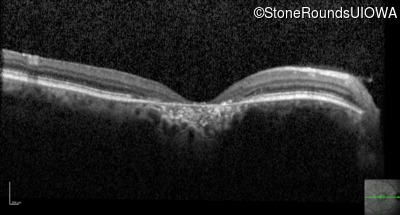

Optical Coherence Tomography - Right - 20/125 -1

Exemplar / OCT Stack